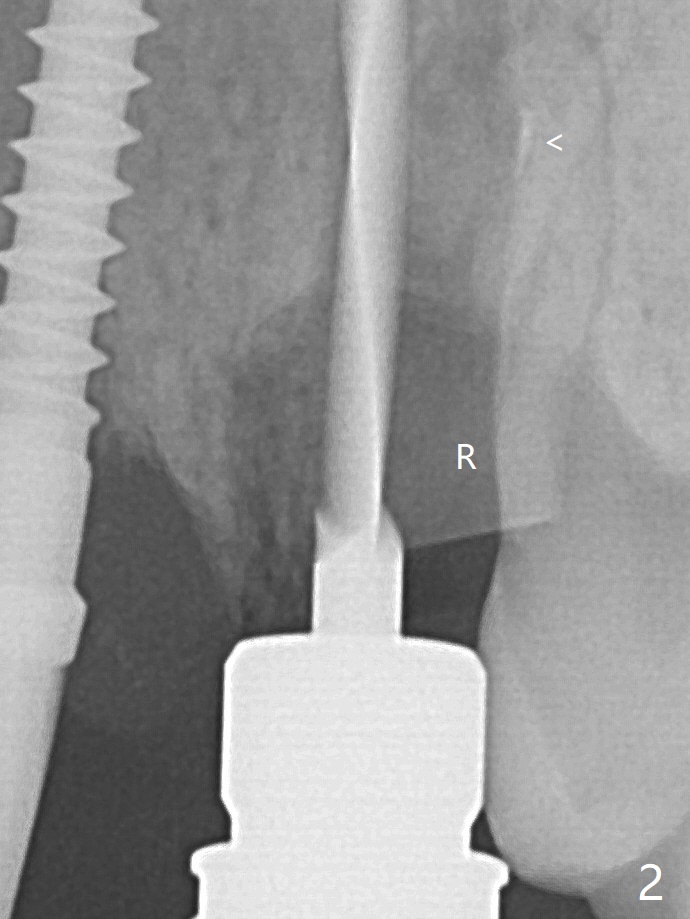

The socket shield at #11 is apparently incomplete, since the apical gutta percha (Fig.2 <) and the apex of the root (Fig.2,3 R) are not removed. The bone is hard when a 1.6 mm drill is being used (Fig.2) as the apical native bone is almost exclusively composed of the cortices. Two of the apical threads of 3.5x13 mm implant are bent, while the implant is placed deeper than the osteotomy (Fig.3,7). After placement of a 4.5x15 degrees A (2mm) angled abutment and Vanilla graft (Fig.7 *), an immediate provisional is fabricated. There is smooth transition from the grafted bone to the native bone 4.5 months postop (Fig.10). Low Magnification, High Magnification of Fig.7,10.